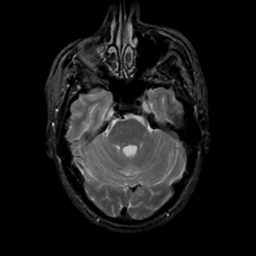

MR Study #12, May 12, 1991 -- Slice #14

[Home][Help][Clinical][Tour 1][Tour 2] Slice 14